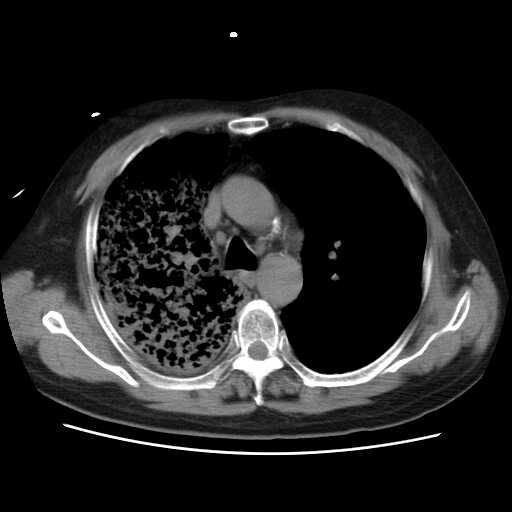

病变从8.11-8.17明显改变,增多,以蜂窝状改变为主,类蜂窝肺,似弥漫性肺泡癌,但是病变进展太快,不符合弥漫性细支气管肺泡癌。因此考虑为特殊微生物感染,多以霉菌类常见,建议细菌微生物学检查。

疑点二:影象表现怪异,大片阴影内见多发筛孔征,如何解释.

间质为主,血管炎性水肿?

军团杆菌肺炎ct表现无特意性,主要—两肺浸润性 弥漫性病变,并少量胸腔积液。